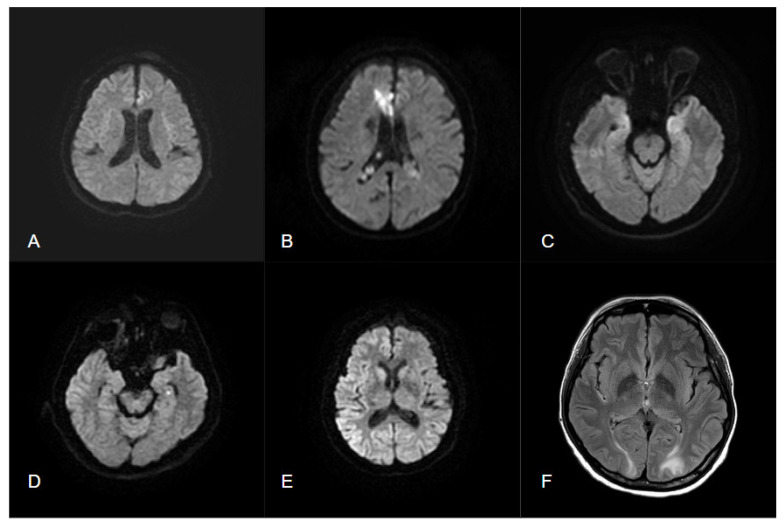

癫痫是一种常见的神经系统疾病;全世界有1%的人患有癫痫。在临床环境中区分癫痫发作与其他急性神经系统疾病可能具有挑战性。大约三分之一的患者患有目前抗癫痫药物治疗不能很好控制的耐药癫痫。手术治疗是潜在的治愈,如果癫痫灶准确定位。扩散加权成像(DWI)是一种先进的磁共振成像技术,它对水分子的扩散很敏感,并提供有关组织微观结构的额外信息。定性和定量分析周周、后周和间期弥散图像有助于癫痫发作的鉴别诊断和癫痫病灶定位。本文综述了DWI的基本原理及其相关技术,如表观扩散系数、弥散张量成像和神经束造影,以及它们在鉴别诊断、癫痫病灶确定和预后预测方面对癫痫的影响。

Epilepsy is a common neurological disorder; 1% of people worldwide have epilepsy. Differentiating epileptic seizures from other acute neurological disorders in a clinical setting can be challenging. Approximately one-third of patients have drug-resistant epilepsy that is not well controlled by current antiepileptic drug therapy. Surgical treatment is potentially curative if the epileptogenic focus is accurately localized. Diffusion-weighted imaging (DWI) is an advanced magnetic resonance imaging technique that is sensitive to the diffusion of water molecules and provides additional information on the microstructure of tissue. Qualitative and quantitative analysis of peri-ictal, postictal, and interictal diffusion images can aid the differential diagnosis of seizures and seizure foci localization. This review focused on the fundamentals of DWI and its associated techniques, such as apparent diffusion coefficient, diffusion tensor imaging, and tractography, as well as their impact on epilepsy in terms of differential diagnosis, epileptic foci determination, and prognosis prediction.